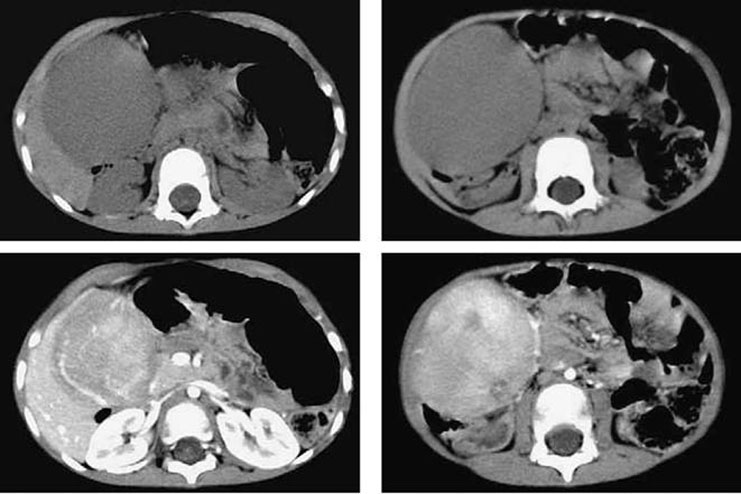

Figura 69-1. Tomografia computadorizada do abdome superior realizada em cortes axiais evidencia volumosa formação expansiva intraperitoneal, circunscrita, de contornos regulares, hipoatenuante na fase sem contraste e que apresenta importante realce na fase arterial.